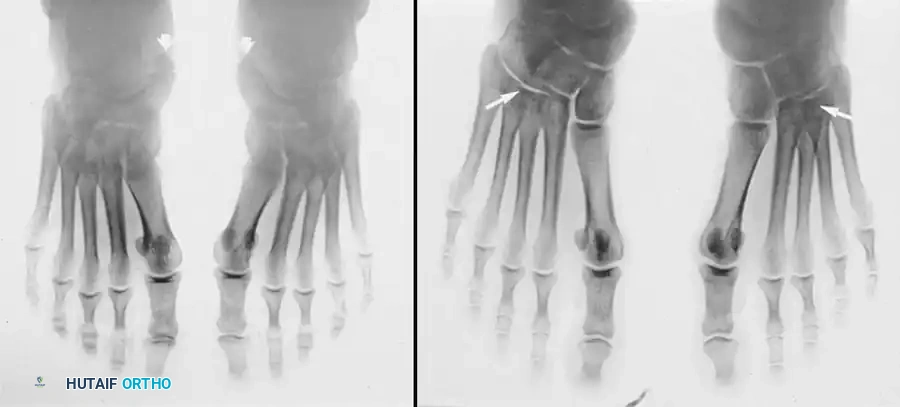

Furthermore, the anteroposterior view may reveal an "opening up" of the metatarsal-cuboid-cuneiform articulations, suggesting a flattening of the longitudinal arch.

Fig. 79-9 B, Arrows point to “opening up” of metatarsal cuboid–cuneiform articulation, suggesting flattening of the longitudinal arch.

Also of significant clinical interest is the pronation of the entire forefoot upon weight-bearing, which is best visualized in the weight-bearing sesamoid view. Subsequent development of hallux valgus is common in these structurally compromised feet.

Fig. 79-9 E, On the symptomatic left foot, the entire forefoot is pronated in the weight-bearing sesamoid view.